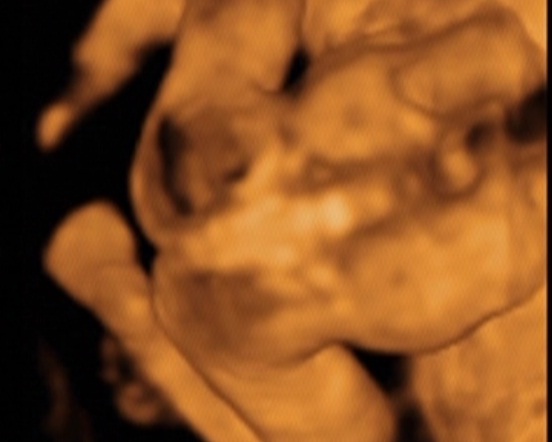

Akkor nem gazdagítjátok tovább a 4D bizniszt?